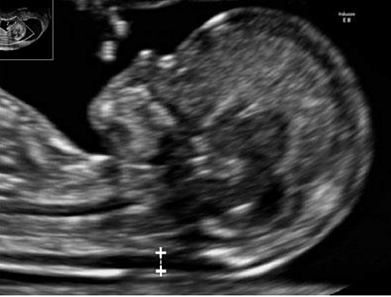

La ecografía obstétrica es una herramienta clave para el seguimiento del embarazo, brindando información detallada sobre el desarrollo y bienestar del bebé. Desde las primeras semanas, permite confirmar la gestación, calcular la edad gestacional y evaluar el crecimiento fetal. A lo largo del embarazo, estas evaluaciones ayudan a monitorear la salud del bebé y detectar de manera temprana posibles complicaciones, asegurando una atención personalizada para la madre y el bebé en cada etapa.

Es la ecografía que se realiza de rutina en el embarazo, indispensable para un correcto seguimiento del mismo, indicándose generalmente una por trimestre. Nos permite evaluar la posición fetal, bienestar fetal, cálculo de líquido amniótico, evaluación de la placenta, cálculo de peso fetal pudiendo corroborar el correcto crecimiento del bebé.

- Idealmente a partir de las 7 semanas desde la FUM. Nos permite: - Calcular el tiempo exacto de gestación - Conformar la viabilidad del embrión. - Corroborar que el embarazo se sitúa correctamente dentro del útero. - Determinar número de fetos